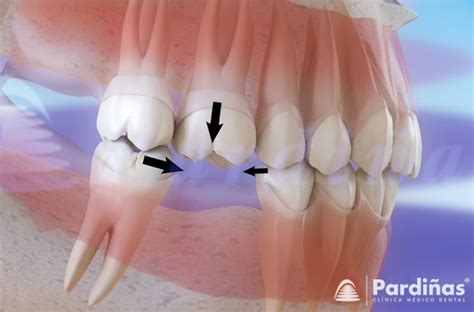

- Extrusión de Dientes Antagonistas: El diente opuesto al espacio vacío puede extruirse al no tener contacto con su antagonista.

- Desplazamiento e Inclinación de los Dientes Adyacentes: Los dientes contiguos al espacio edéntulo tienden a inclinarse hacia dicho espacio.

- Movimiento de Dientes Adyacentes, Cambiando la Oclusión: Esto dificulta la rehabilitación posterior y puede causar problemas en la masticación.